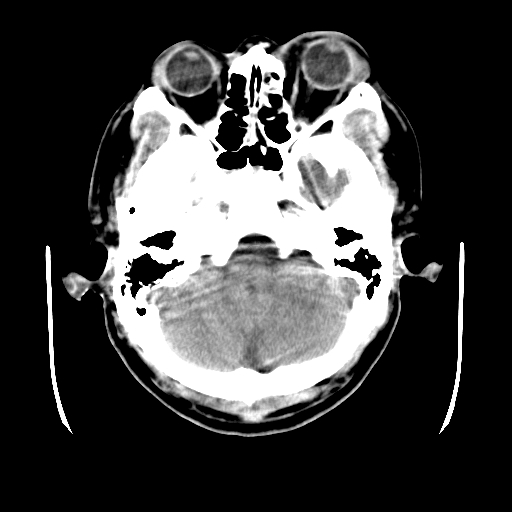

男,51岁,头外伤一小时,呕吐两次。

1)左侧中颅窝蝶骨翼后方硬膜外血肿。2)左侧颞顶部硬膜下血肿。3)蛛网膜下腔出血。4)左侧筛窦及双侧蝶窦炎症(或积血)。5)左侧额部头皮软组织肿胀。